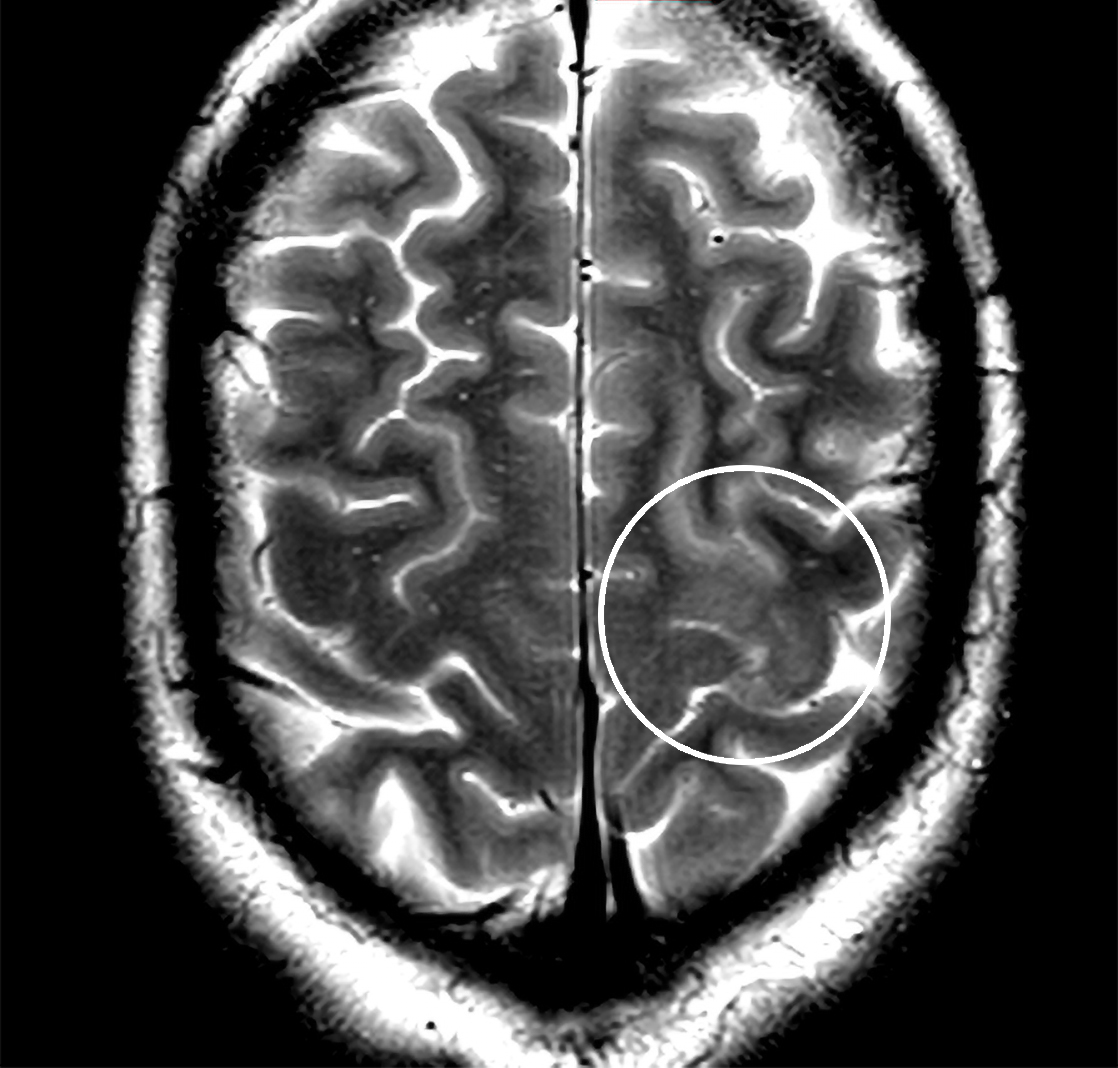

1. En mann i 40-årene med talevansker og ensidig lammelse

En mann i slutten av 40-årene ble innlagt med akutt innsettende slagsymptomer. Utredningen avslørte en sykdom som ofte glemmes, men som forekommer i økende grad og er behandlingstrengende. Les mer her.